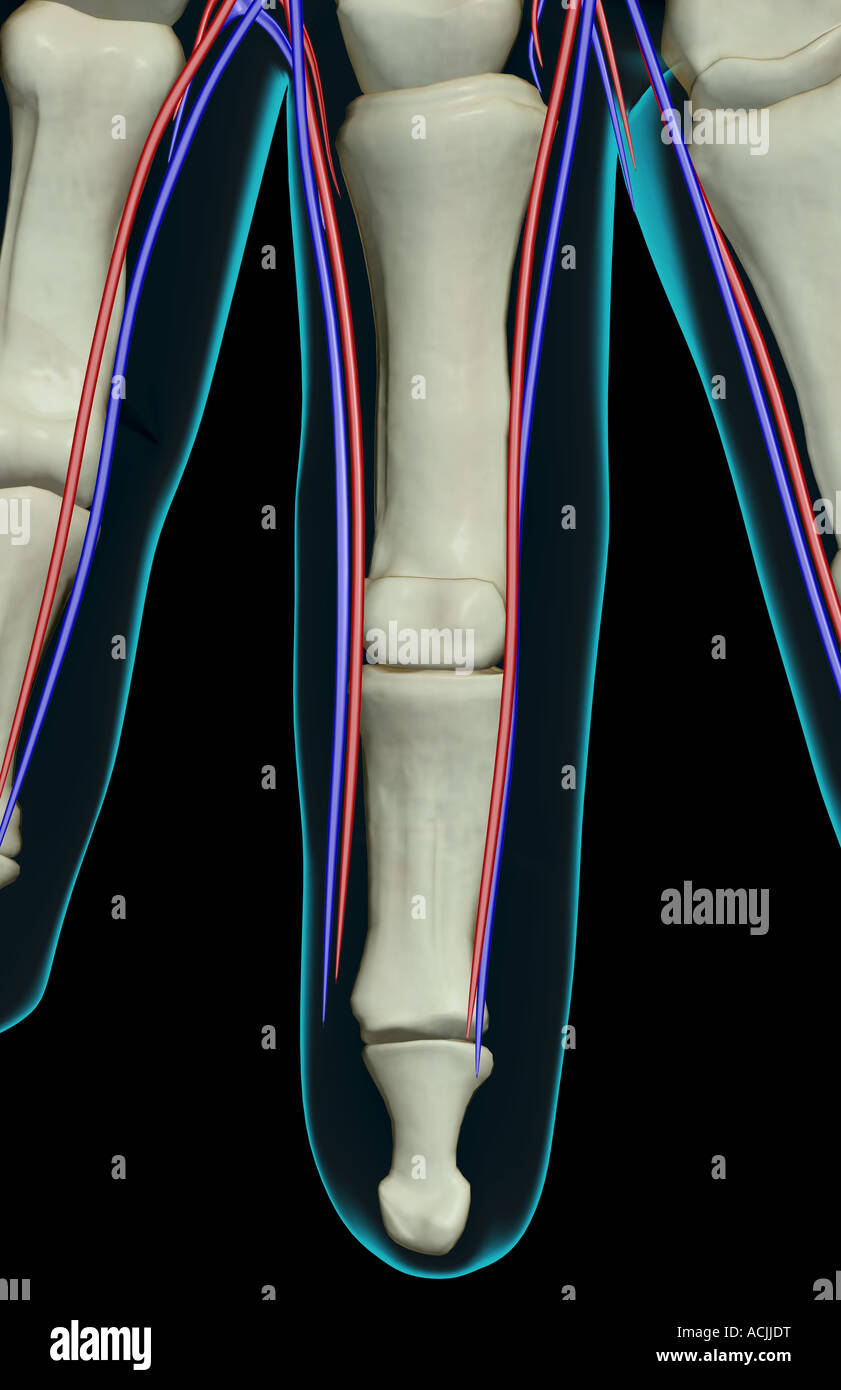

The blood supply of the fingers Stock Photohttps://www.alamy.com/image-license-details/?v=1https://www.alamy.com/stock-photo-the-blood-supply-of-the-fingers-13171139.html

The blood supply of the fingers Stock Photohttps://www.alamy.com/image-license-details/?v=1https://www.alamy.com/stock-photo-the-blood-supply-of-the-fingers-13171139.htmlRFACJJDT–The blood supply of the fingers